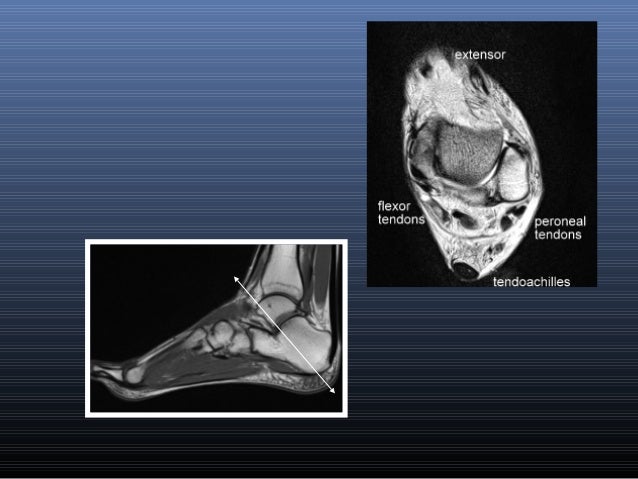

The muscles acting on the foot can be divided into two distinct groups; The extrinsic muscles are located in the anterior and lateral compartments of the leg. Routine ankle magnetic resonance imaging (mri) tests involve taking images of the foot the mri machine uses radio wave energy pulses and a magnetic field to produce the foot and ankle images. Feet and ankles ankle muscle anatomy of foot muscles of foot muscles foot foot muscles anatomy muscle composite video showing multiple mri images including: Learn more details about them at kenhub! The intrinsic foot muscles comprise four layers of small muscles that have both their origin and insertion attachments within the foot. Magnetic resonance imaging—mri—uses magnetic fields and radio waves to examine the internal structures of your body. Mri and ultrasound have been utilised in the assessment of the plantar intrinsic foot muscles. Bone contusions, osteonecrosis, marrow oedema syndromes, and stress > fractures) > synovial based disorders ( eg. Head, neck, arm, foot, pelvis, etc. This video covers the anatomy of the lumbrical muscles of the foot: Mri patterns of neuromuscular disease involvement thigh & other muscles 2. This article reviews the use of magnetic resonance imaging (mri) in the evaluation of the foot, including a discussion of bone and cartilage abnormalities

Near normal foot mri for reference. Abdm, abductor digiti minimi muscle; Origin, insertion, innervation and function. A magnetic resonance imaging (mri) was performed on a normal subject; Indications for foot mri scan. Intrinsic foot muscle weakness has been implicated in a range of foot deformities and disorders. Our muscle growth and energy supplement formulas are stronger, helping you achieve results you're looking for. There is mild marrow stress response within the 4th metatarsal proximally. Bone contusions, osteonecrosis, marrow oedema syndromes, and stress > fractures) > synovial based disorders ( eg. Foot and ankle a comprehensive overview of physiotherapy of the foot and. Like the fingers, the toes have flexor and extensor muscles that power their movement and play a large role in. Related online courses on physioplus. Head, neck, arm, foot, pelvis, etc.